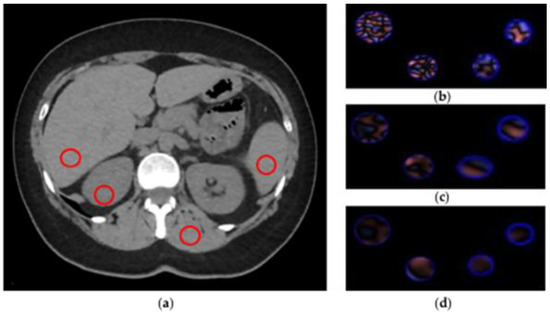

CTTA extracted from abdominal CT is a first-order radiomic feature based on a statistical method that quantifies the heterogeneity of a ROI, analyzing the intensity of pixel frequency and then extracting the following histogram parameters: mean intensity, standard deviation, entropy, kurtosis, skewness, and mean value of positive pixels (MPP). For CTTA, spatial filters, denoted by spatial scaling factors (SSFs) of 0 to 6, were applied. SSF 0 indicates no filtration; SSFs 2, 4 and 6 indicate 2, 4 and 6 mm radii, which represent fine, medium and coarse filters, respectively. These filters analyze the ROI at a different scale with object radii of different sizes. All the parameters extracted were assessed with and without altering the SSF with a Laplacian of Gaussian spatial band-pass filter to highlight features at different anatomic spatial scales at fine, medium and coarse texture. Figure 3 shows the filtration-histogram-based CTTA of FBP reconstruction and ASIR-V 100.

Figure 3.

CT texture analysis (CTTA) process. (a) Regions of interest (ROIs) placement. (b–d) Filtration-histogram statistic-based method corresponding to fine, medium and coarse texture scale of ROIs (area 1 cm2), respectively.